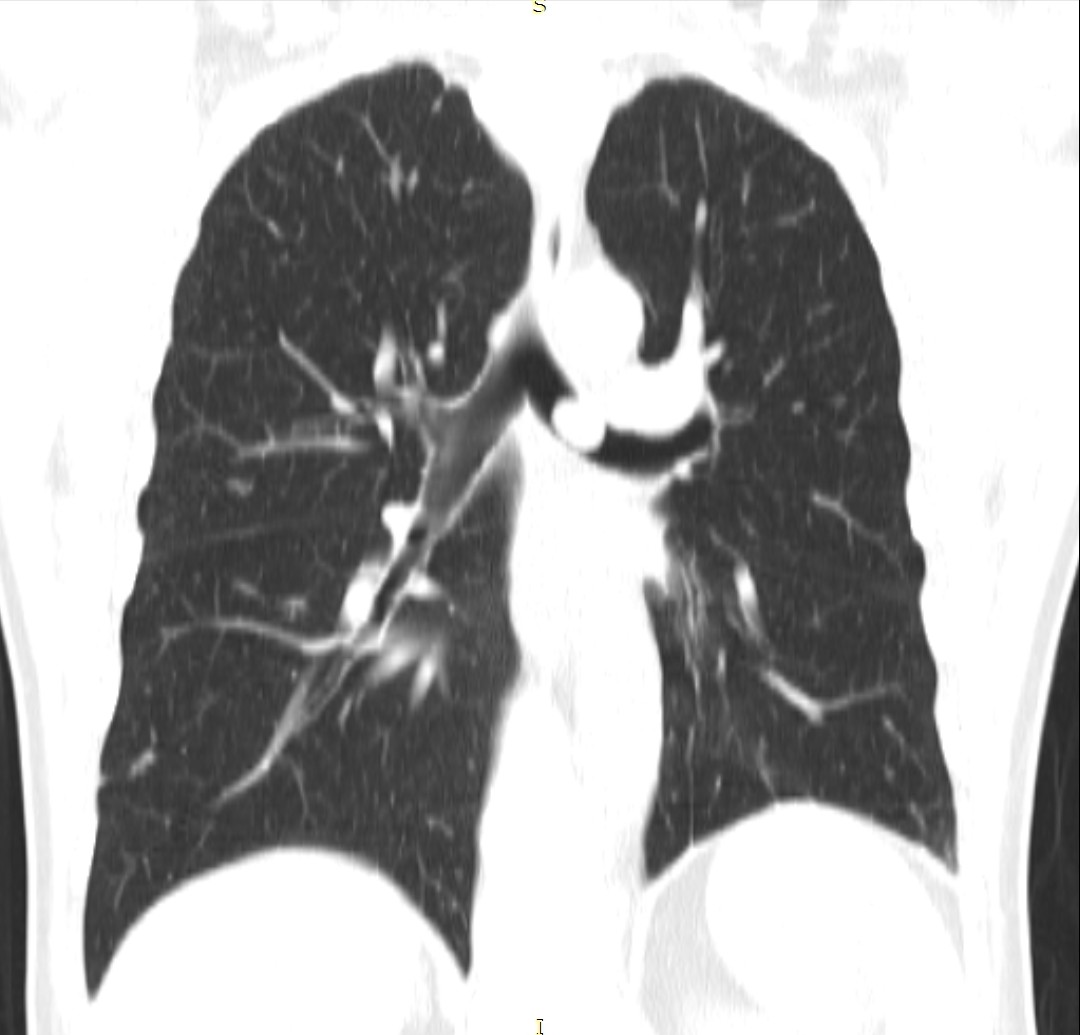

- გულმკერდის კტ (Coronal) რეზექციამდე 2 კვირით ადრე

სიმსივნური წარმონაქმნი მარცხენა მთავარ ბრონქში.

აღინიშნება მარცხენა ფილტვის თითქმის სრული ატელექტაზი.